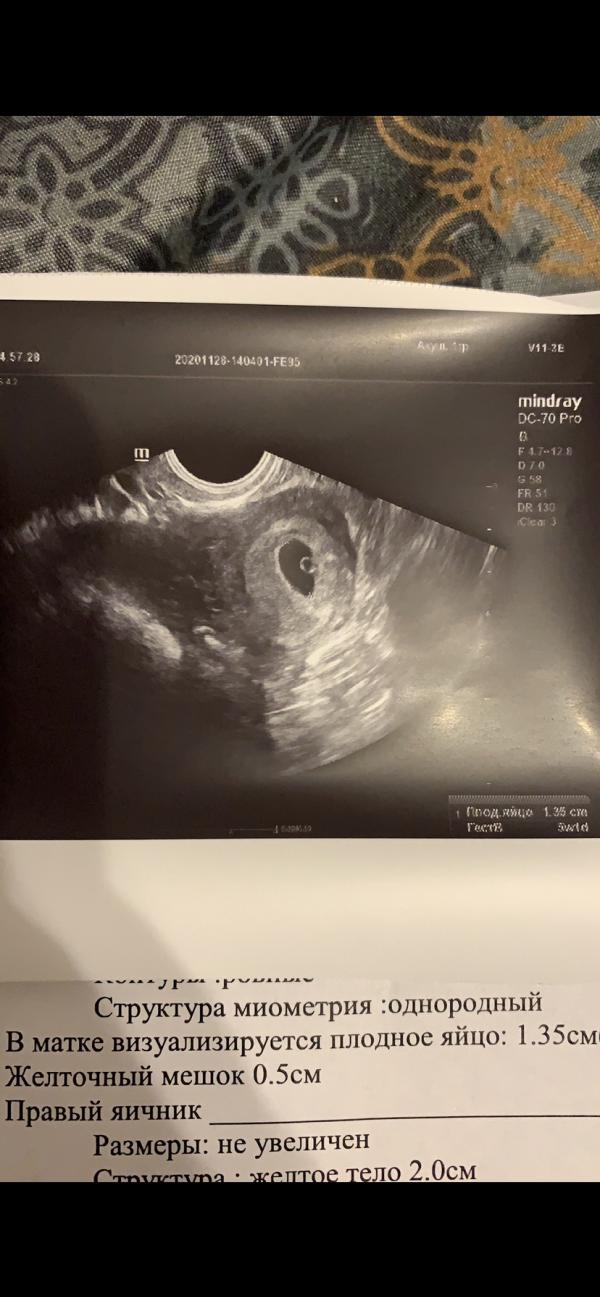

Смотрю на свое самое первое узи в 4-5 недель и вообще не представляю🥹 там сидит моя доченька Варя👼🏼 кто бы мог подумать, что она будет такая забавная, веселая, добрая и улыбчивая девочка❤️❤️❤️